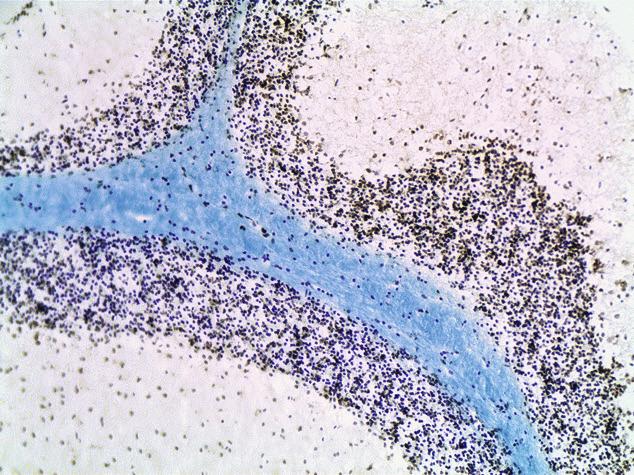

Mouse brain was isolated and formalin fixed/paraffin embedded (FFPE). After sectioning, the tissue was treated with Click-iT TUNEL Colorimetric reagents and Luxol Fast Blue Stain. Due to hypoxic conditions, dead and dying apoptotic cells (dark brown) are clearly visible. Image captured using the 20X objective on the EVOS™ FL Auto Cell Imaging System.